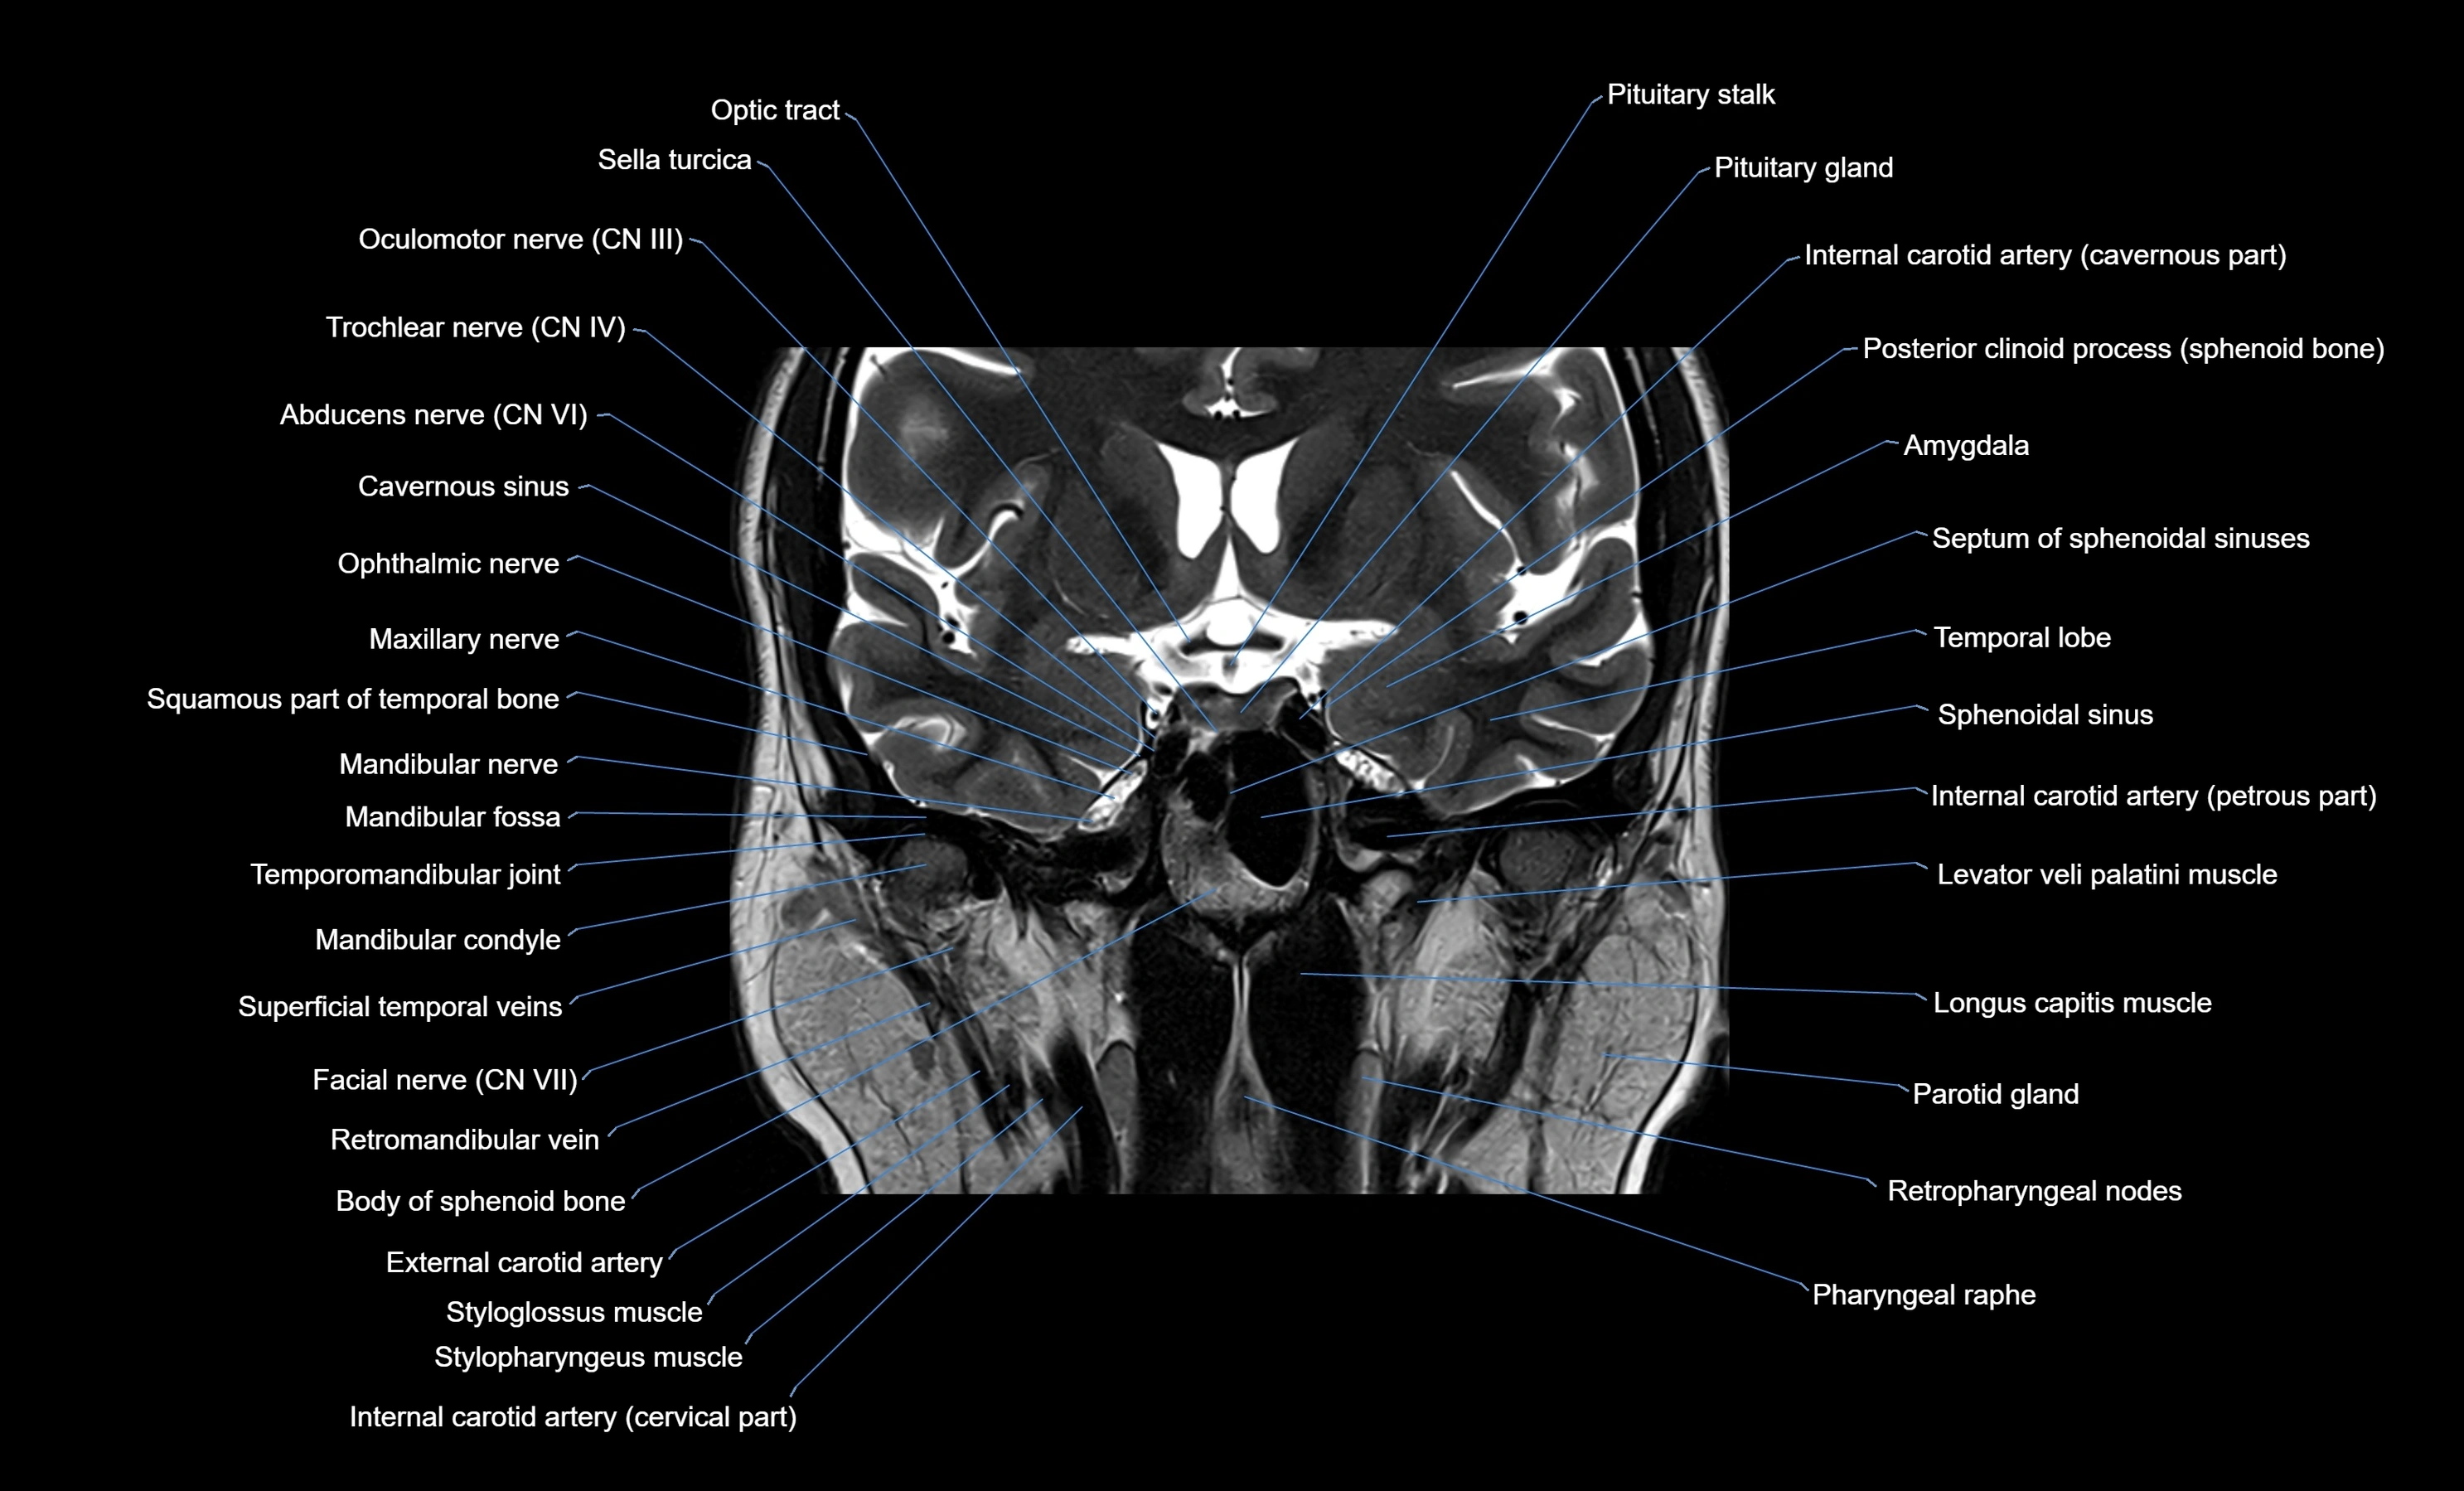

- Optic chiasm

- Sella turcica

- Oculomotor Nerve (Cranial Nerve III)

- Trochlear nerve (Cranial nerve IV)

- Abducens nerve (Cranial nerve VI)

- Internal carotid artery (cavernous part)

- Internal carotid artery (petrous part)

- Levator veli palatini muscle

- Longus capitis muscle

- Mandibular condyle

- Mandibular fossa

- Mandibular nerve

- Maxillary nerve

- Meckel’s cave (Trigeminal cave)

- Retromandibular vein

- Parotid gland

- Retropharyngeal lymph nodes

- Styloglossus muscle

- Stylopharyngeus muscle

- Internal carotid artery (cervical part)